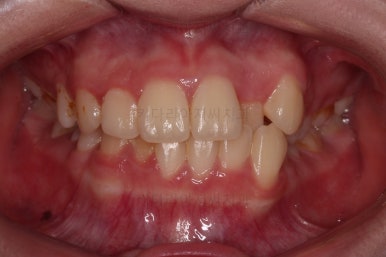

부산교정치료 초진 시 입안의 모습입니다.

치아가 전반적으로 삐뚤고, 덧니가 두드러져 보이네요.